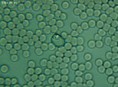

Mnohé štúdie dokazujú pozitívny efekt Bioquantu - jeho laserového žiarenia na postupnú elimináciu baktérií, vírusov či lariev parazitov migrujúcich v krvnom riečišti. Ide najmä o normalizáciu imunity, špecifickej i nešpecifickej. Navyše termodynamický efekt laseru pri ožarovaní krvi, ktorý síce náš organizmus nevníma a ľudské bunky neohrozuje, spôsobuje zvyšovanie termodynamickej teploty najmenších štruktúr - teda mikroorganizmov. Tieto následne ničí aktivovaná imunita a zvýšená baktericídna aktivita krvného séra. Sú zaznamenané pozitívne efekty pri vírusoch HIV/AIDS, vírusoch encefalitídy, pri borelióze, pri prevencii chrípky. O účinkoch na baktérie svedčí aj vysoká účinnosť pri výskytu akné baktérií. Prostredníctvom aktivácie porfírinov sa uvoľňujú voľné radikály a tým zabíjajú baktérie zvnútra..

Laserové ožarovanie krvi navodzuje i úpravu pomerov populácie T helperov a T supresorov smerom k normalizácii a úprave celkového počtu T lymfocytov a vyvoláva zmenu aktivity enzýmov imunokompetentných buniek. To je dôležité pre celom rade ďalších ochorení.